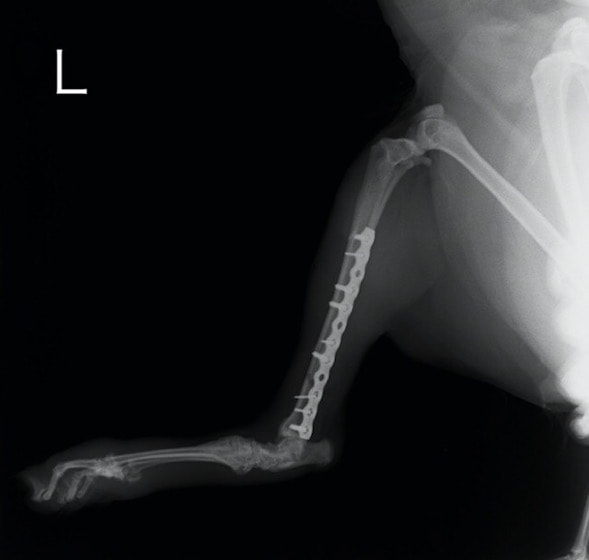

症例:交通事故による椎体脱臼

柴犬:9歳、避妊雌

交通事故直後、胸腰部に激しい疼痛、両後肢に完全麻痺を認め、シェフシェリントン徴候を呈していました。レントゲン検査において、第11-12胸椎間の脱臼が認められました。

脊髄の減圧、脊柱管の再構築・安定化を目的に、片側椎弓切除術およびMatrixMANDIBLE Plateによる椎体固定を実施しました。

隣接椎体を架橋するようにプレートを設置しました。

術後レントゲン写真